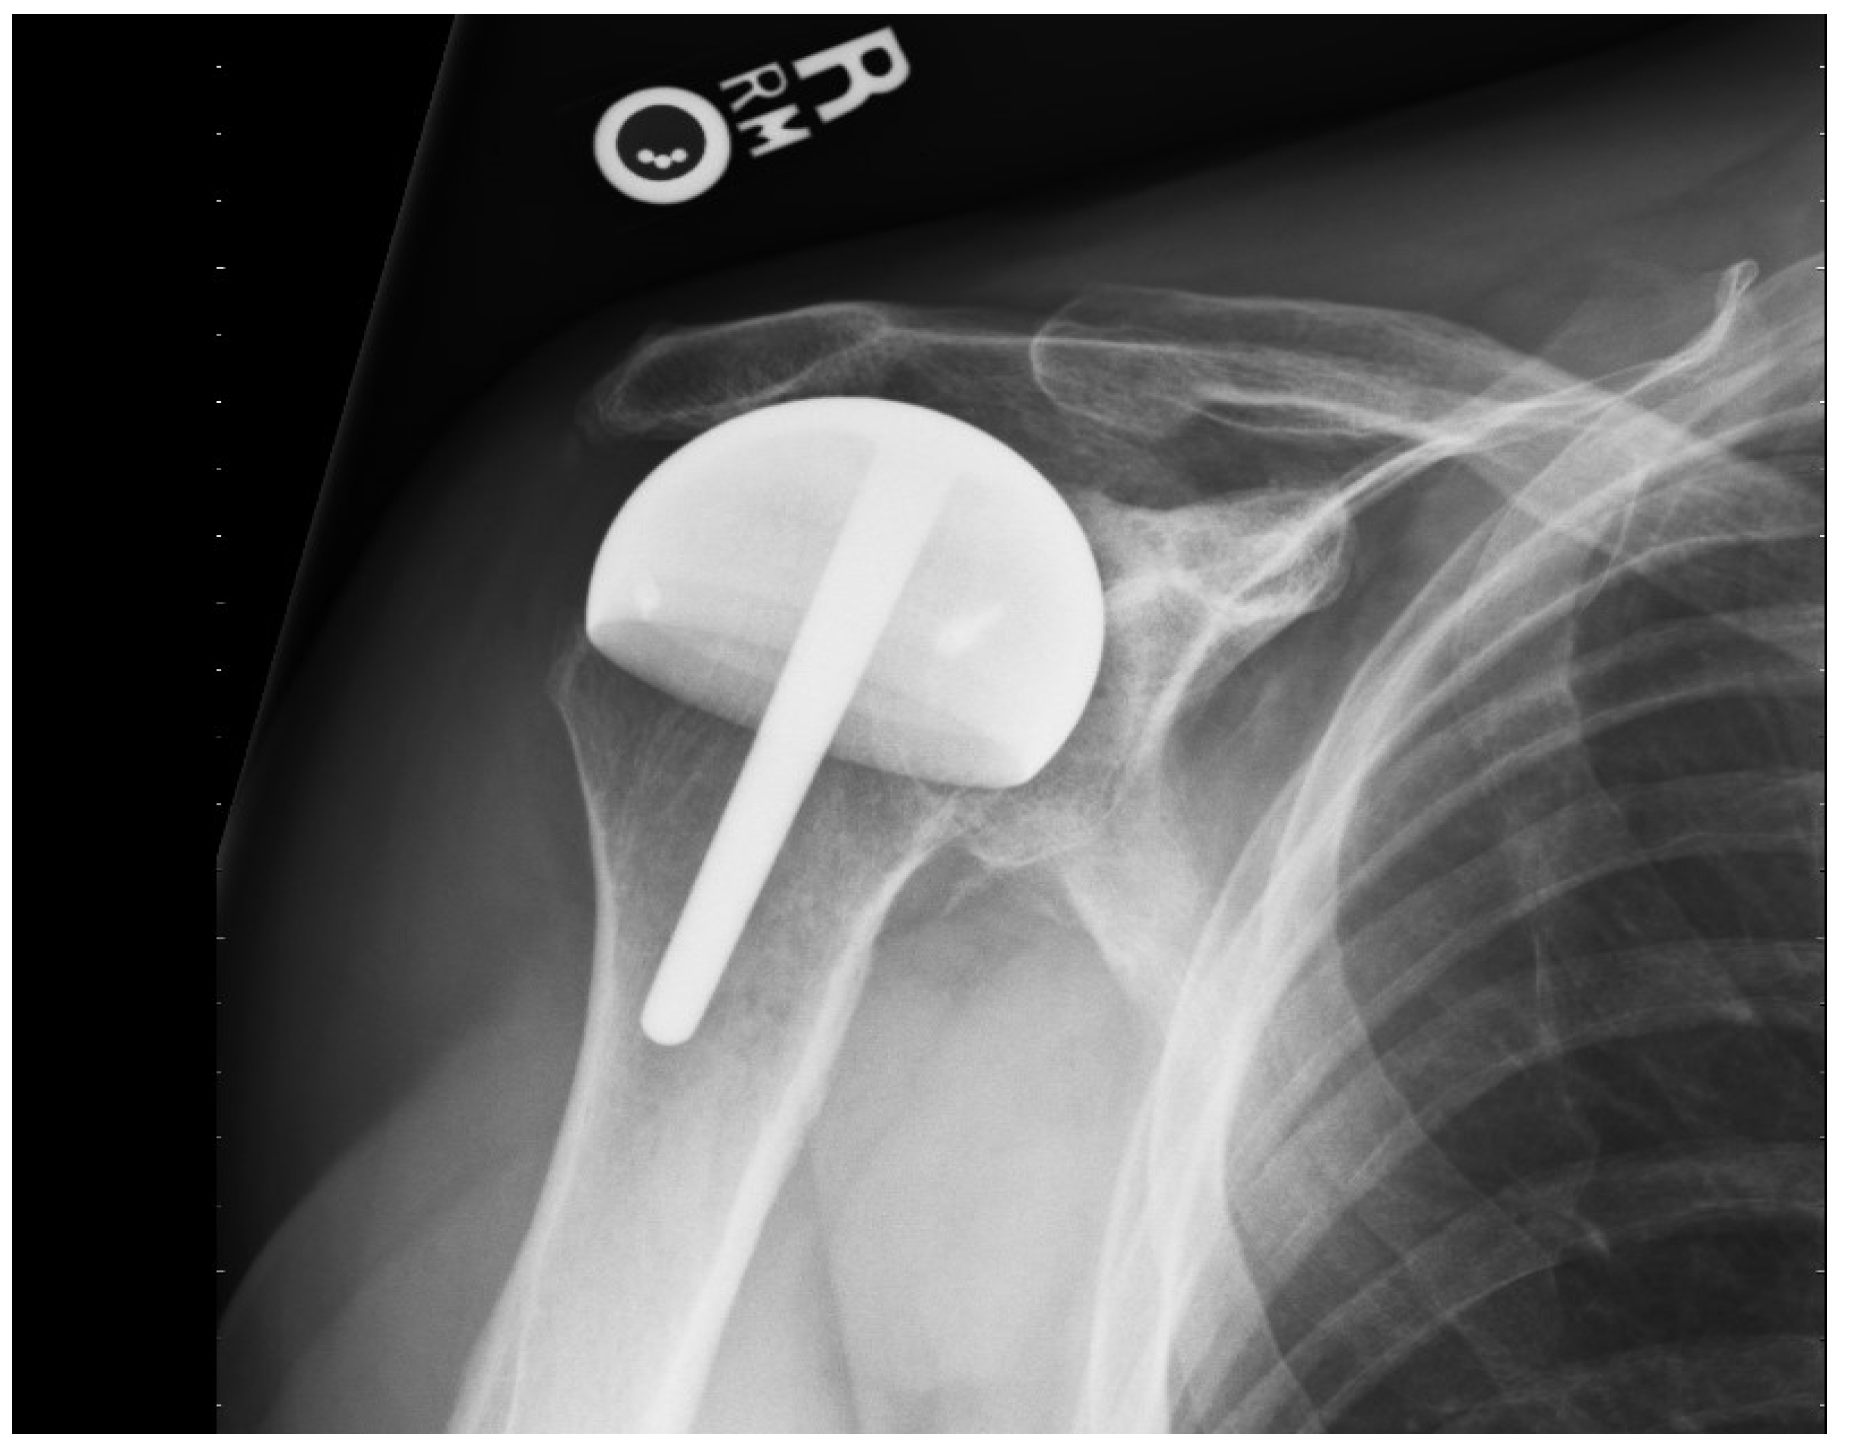

For the 67 rotator cuff arthropathy patients, the mean patient age was 67 (SD 10.6 years, range; 51–83 years): 46 (68%) were men, 21 (32%) were women, and 44 (67%) had prior surgery (Figure 3).

Figure 3.

This AP shoulder radiograph shows a shoulder resurfacing performed with a full coverage component covering the tuberosities and articulating with the acromion and glenoid.